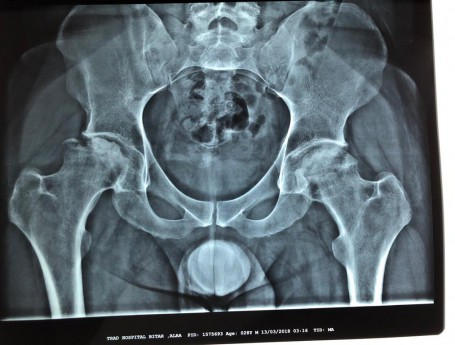

Bilateral Total Hip Arthroplasty Anterior Approach

• Bilateral Total Hip Arthroplasty Anterior Approach